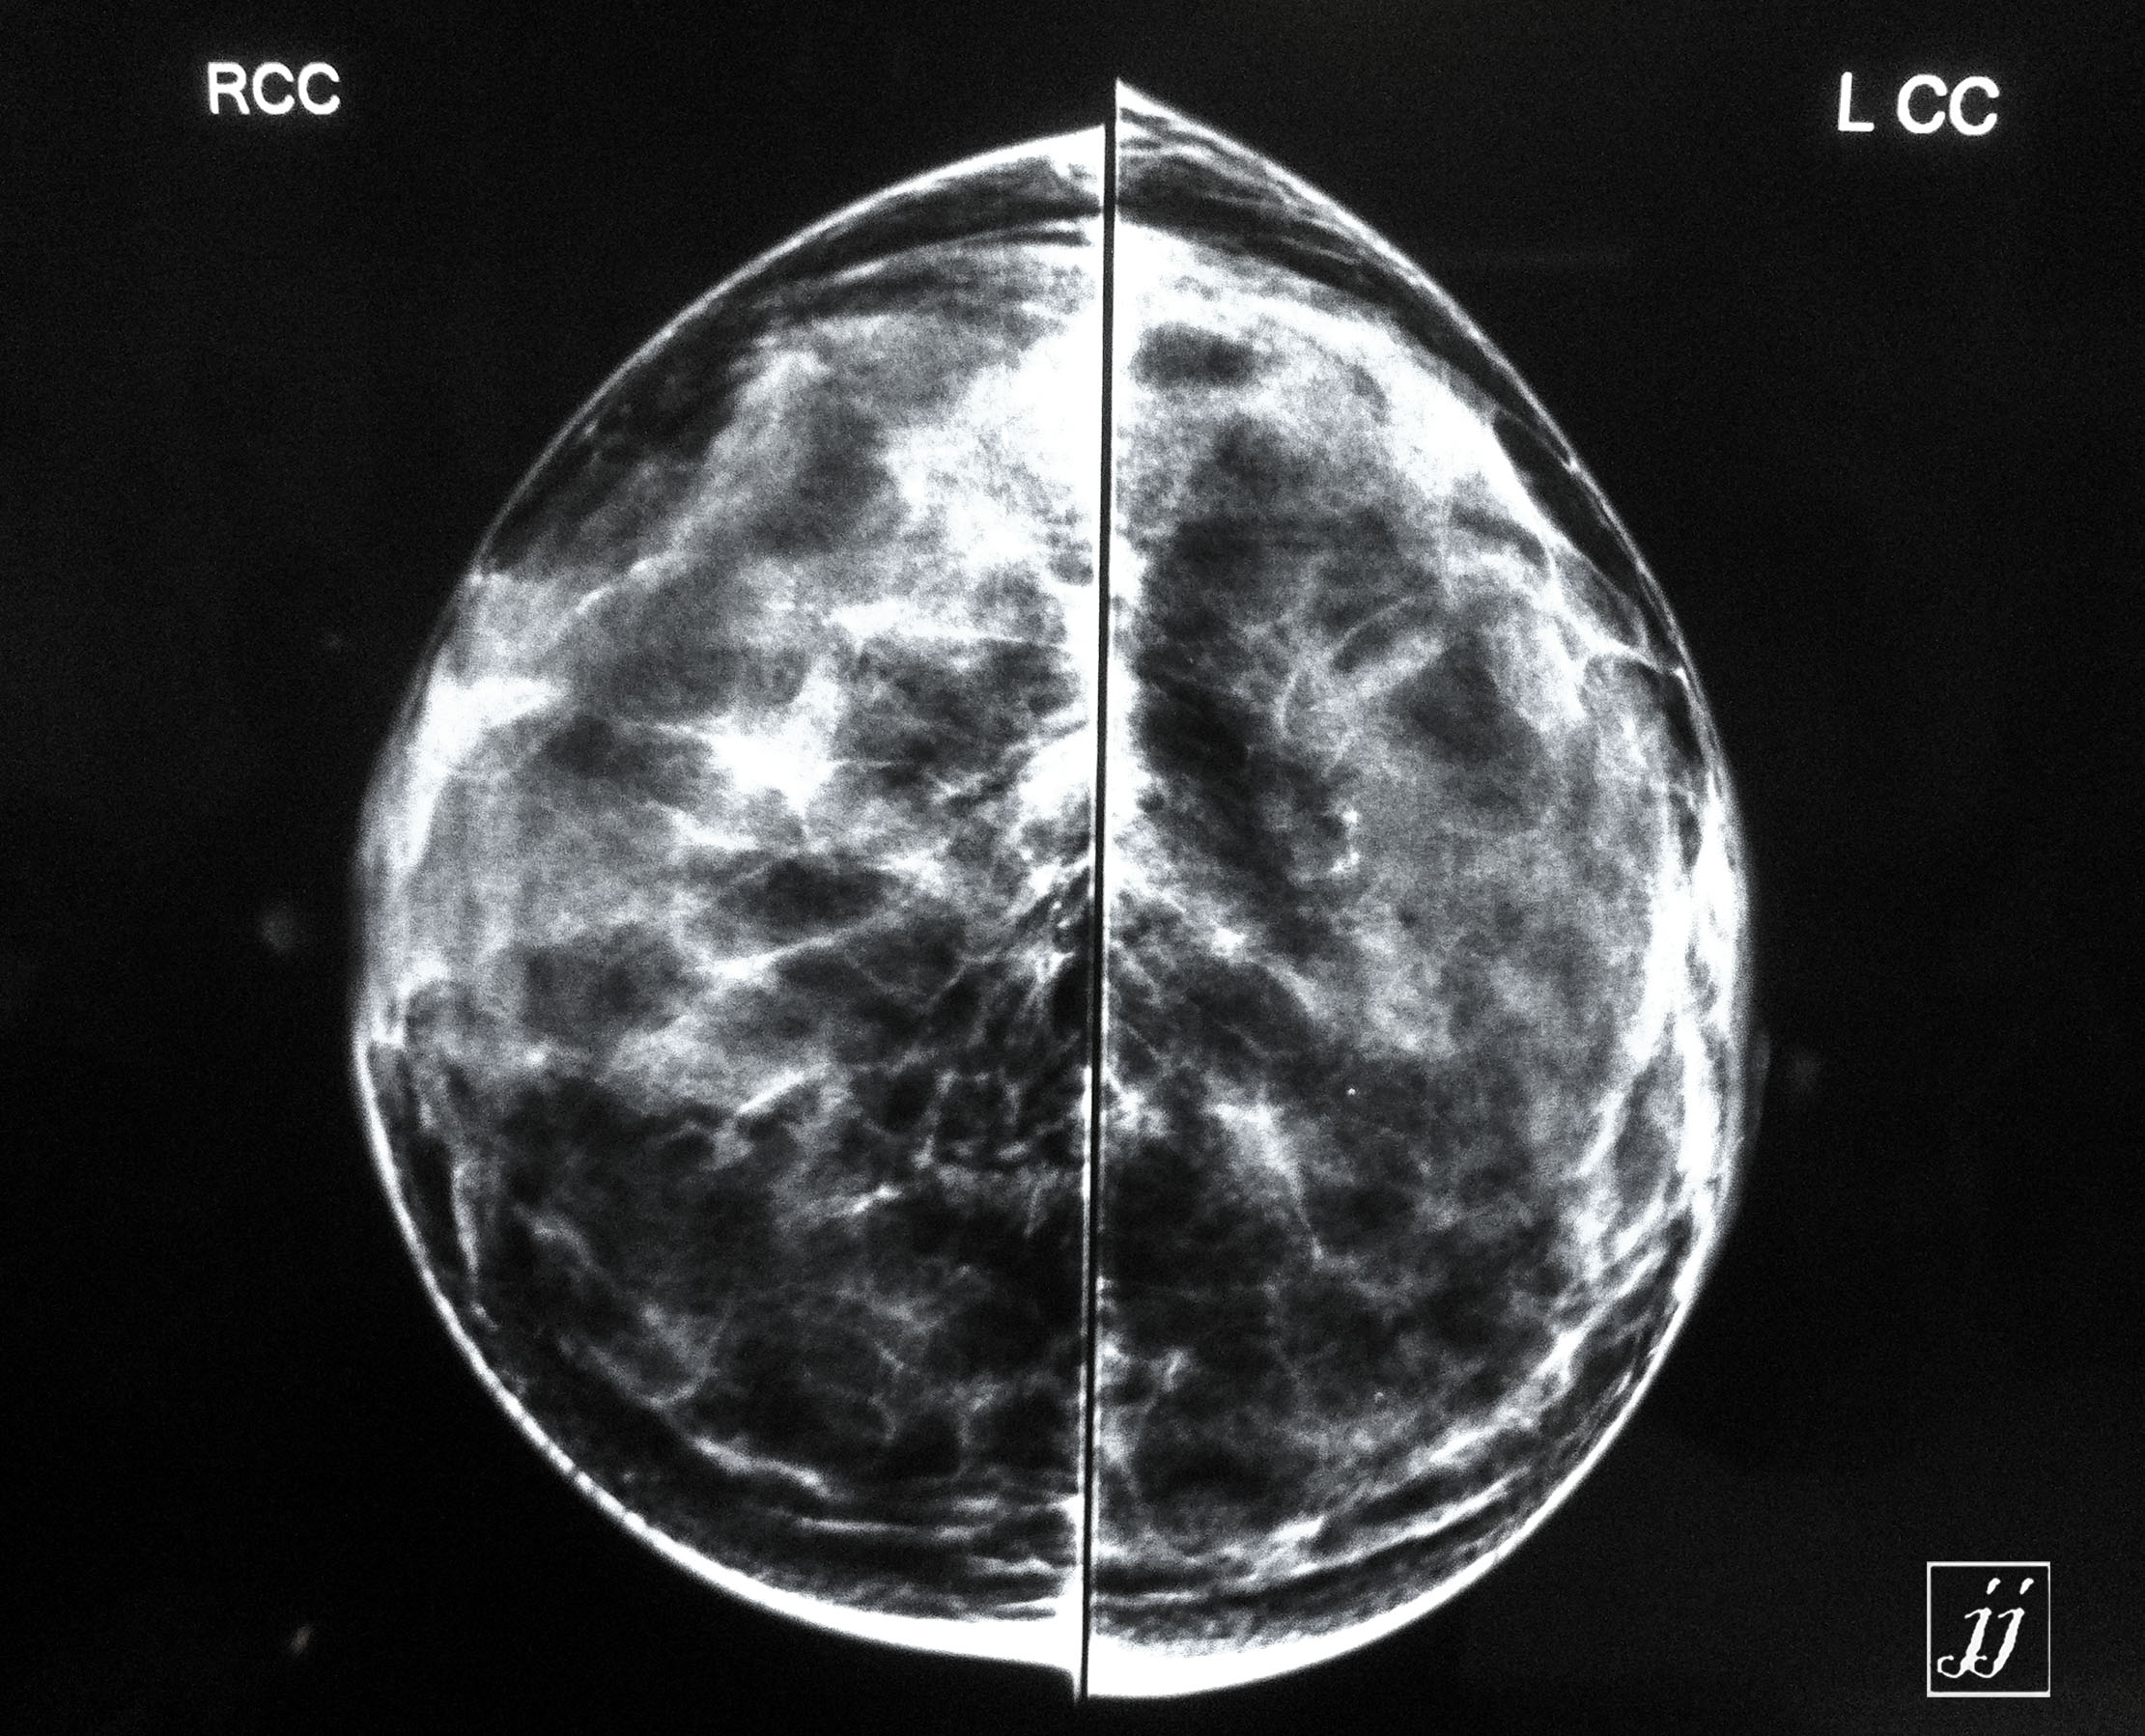

Breast- breast cyst (2)